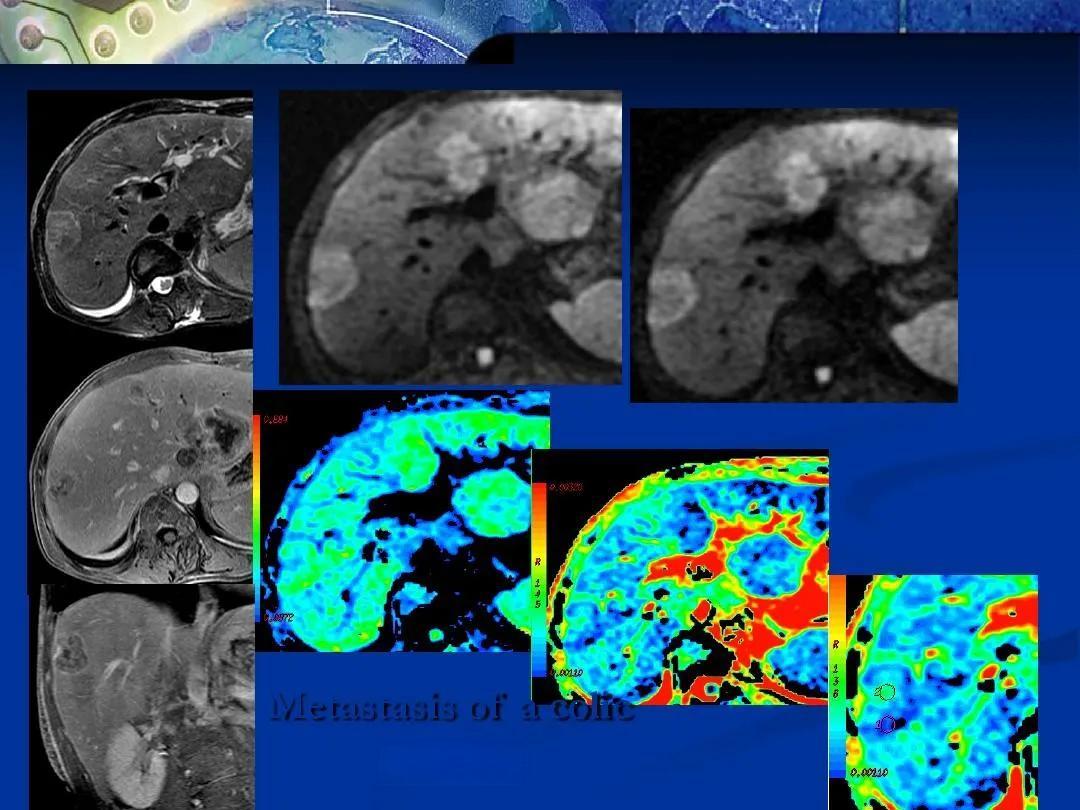

磁共振弥散技术是一种基于水分子在人体内自由弥散运动的成像技术。与传统的核磁共振成像(MRI)不同,磁共振弥散成像(DWI)能够提供基于脑生理状态的信息,对诊断急性脑梗死等疾病具有极高的敏感性和特异性。更重要的是,这项技术为我们提供了一种无创的方法来观察大脑内部的微观结构和功能。

在临床应用方面,磁共振弥散技术已经显示出巨大的潜力。它不仅能够早期诊断急性脑梗死,还能帮助区分不同类型的脑肿瘤。蒲慕明提到:“对于非常简单的大脑功能,包括我们怎么样看到外界的物体,怎么样了解听觉系统、视觉系统、还有情绪系统,我们的心情是怎么变化,是什么脑区控制的,这大致都有一些了解。”